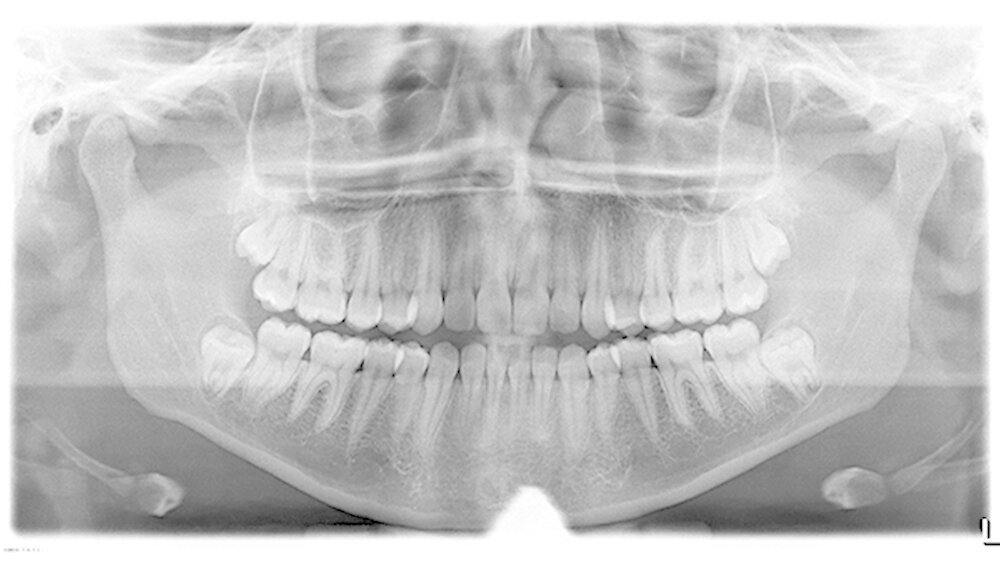

Eine 19-jährige Patientin wurde zur Entfernung der komplett retinierten verlagerten Weisheitszähne 18, 28, 38 und 48 überwiesen. Die Patientin war anamnestisch unauffällig, war aber Raucherin.

Aufgrund der engen Lagebeziehung der Weisheitszähne 38 und 48 zum Nervus alveolaris inferior (Abbildung 1) wurde zur weiterführenden Diagnostik eine digitale Volumentomografie (DVT) in der Praxis von Dr. Burkard Langenfeld in Friedrichshafen durchgeführt (Abbildungen 2 und 3).